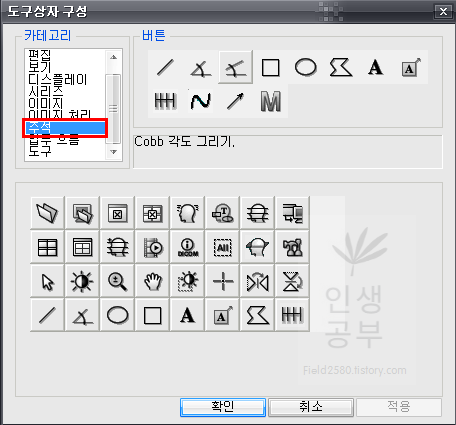

저 같은 경우는 Cobb 각도를 많이 사용하기 때문에 우선 Cobb각도 설정하는 방법에 대해서 알려드리겠습니다. 카테고리칸에 주석을 눌러주면 다양한 각도나 선, 모양을 그릴 수 있는 버튼이 나옵니다. 그중 상단 3번째 있는 버튼이 Cobb각도 그리기 입니다.

Cobb각도 그리기 버튼을 클릭해주고 아래로 쭉 내려주면 현재 사용하고 있는 도구상자에 Cobb각도 그리기 버튼이 추가되는 것을 확인하실 수 있습니다.